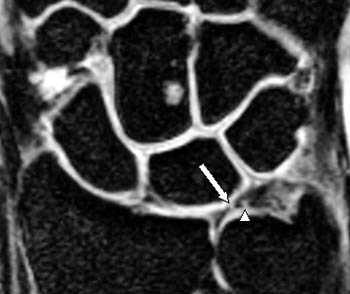

МРТ кисти. Разрыв радио-ульнарной связки - части треугольного фиброзно-хрящевого комплекса

МРТ кисти. Разрывы диска треугольного фиброзно-хрящевого комплекса.